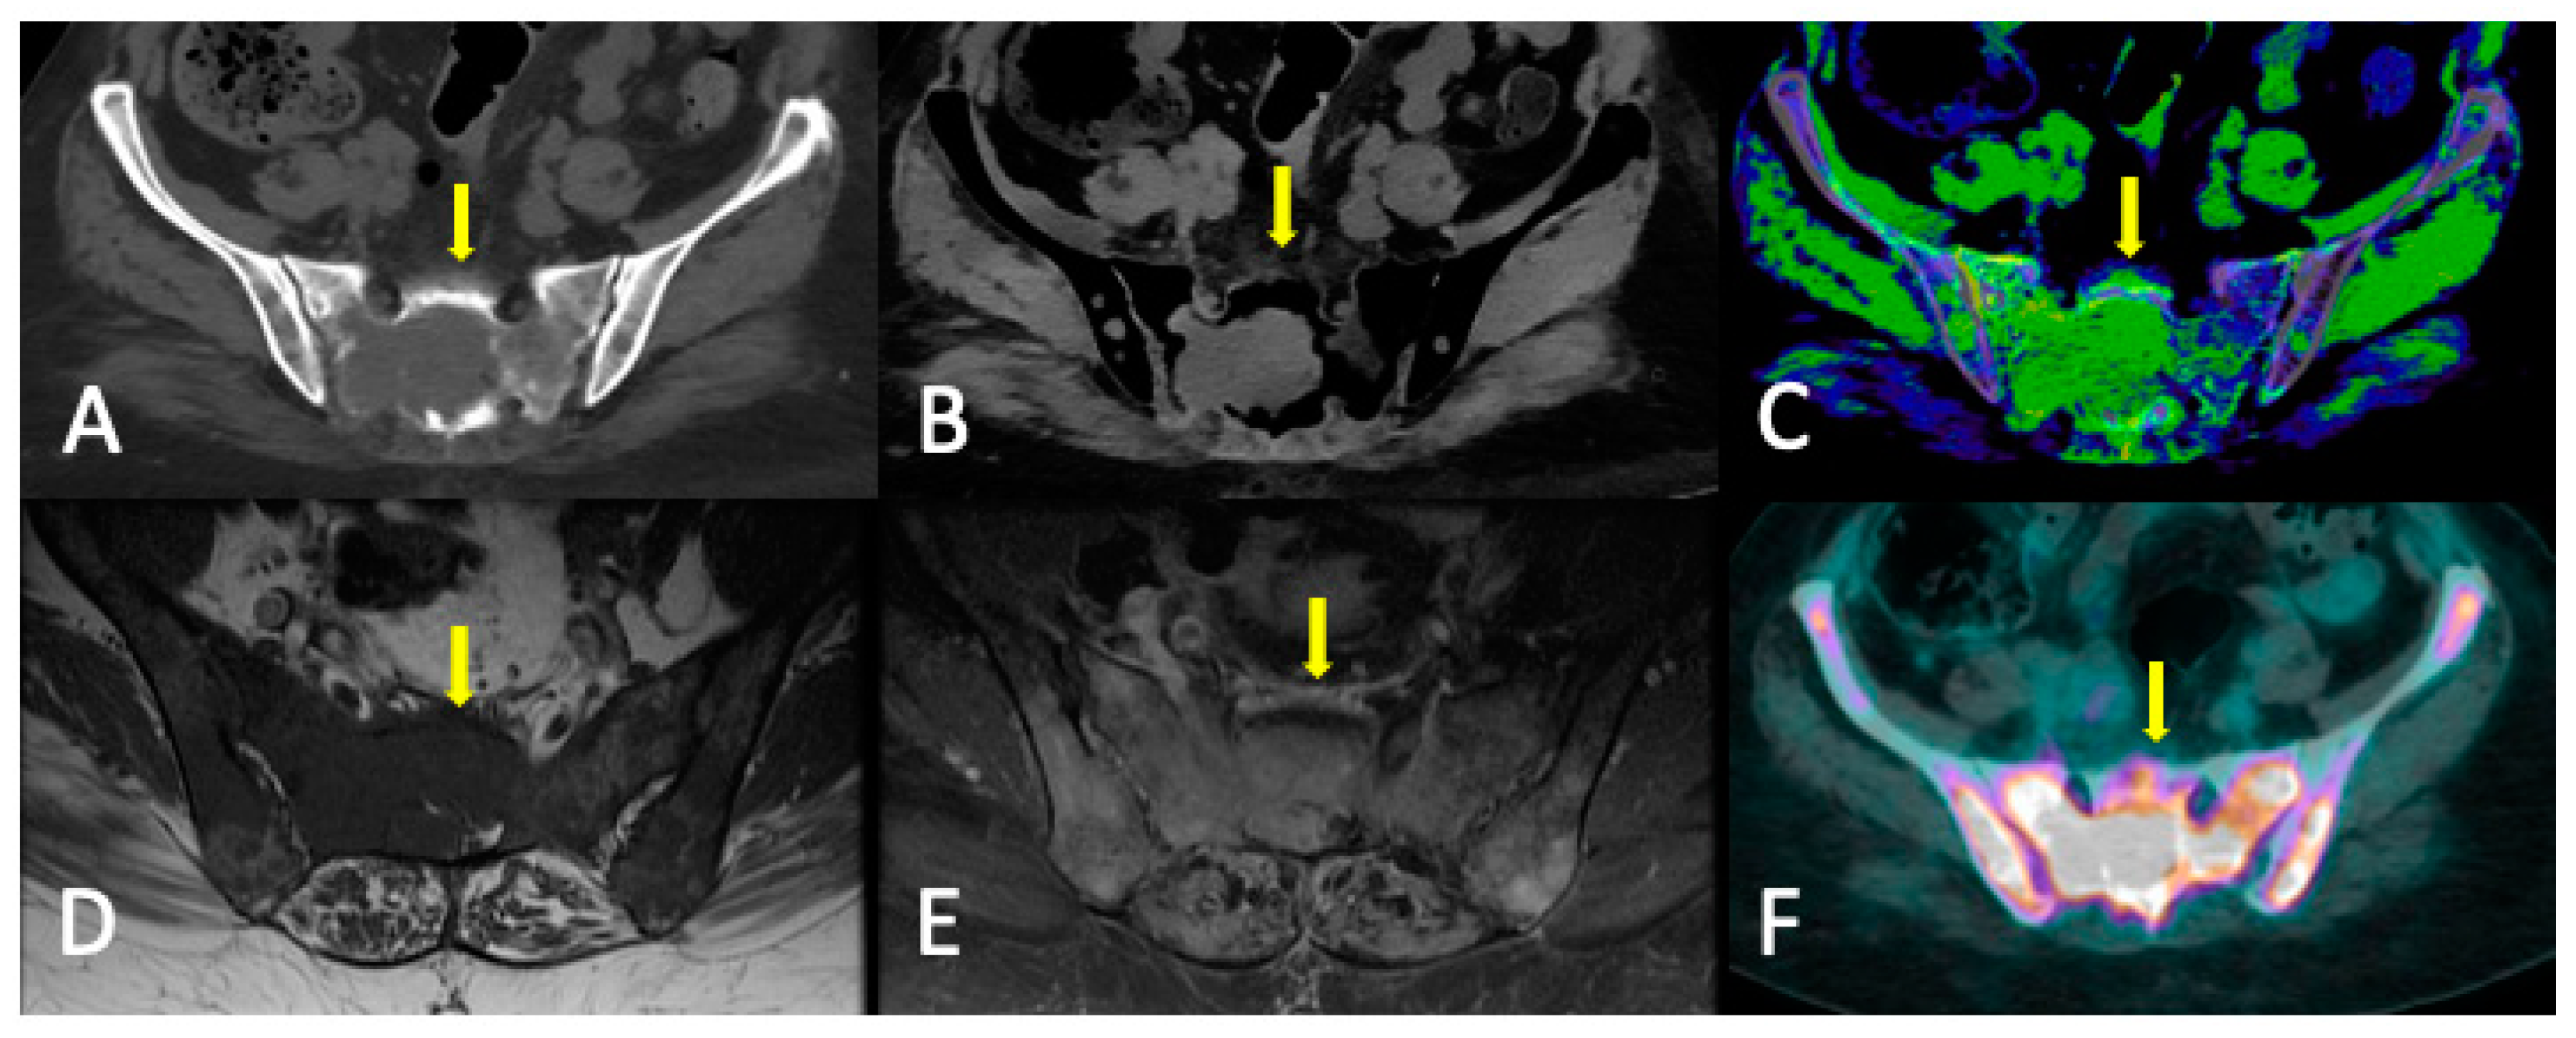

3.3. Role of DECT

3.4. DECT vs. Conventional CT